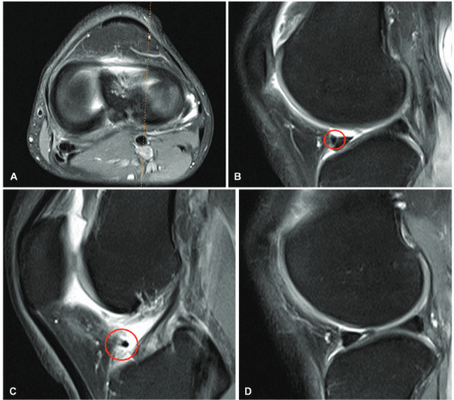

Косая мениско-менисковая связка – еще одна анатомическая структура, соединяющая мениски, встречается заметно реже (в 2–4 % случаев) и соединяет противоположные рога разных менисков.

Дифференциальный диагноз проводится с целью исключения смещенного лоскута мениска или разрыва по типу «ручки лейки», имитация которых возможна на сагиттальных срезах в центральном отделе сустава.

Для подтверждения нормы необходимо проследить ход структуры в аксиальной проекции [10, 15, 16] (рис. 4).